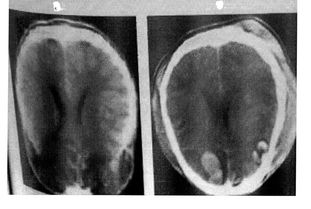

CT是利用x线的一种特殊性质对人体进行的断层检查技术,它的密度分辨率较高,所以很容易发现一些异常的病灶。

1、CT的特点:CT是计算机体层摄影的简称,1969年设计成功,具有检查方便、安全、无痛苦、无创伤的特点。

CT片图像清晰、分辩力高、解剖关系明确、病态显影清楚。

CT即电子计算机断层扫描,它是利用精确准直的X线束、γ射线、超声波等,与灵敏度极高的探测器一同围绕人体的某一部位作一个接一个的断面扫描,具有扫描时间快,图像清晰等特点,可用于多种疾病的检查。